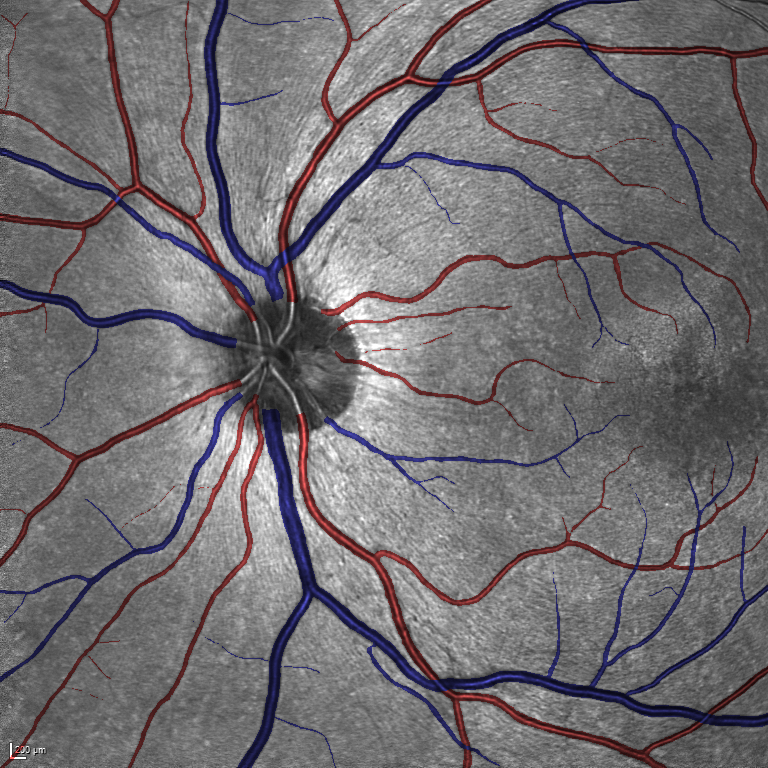

Table V presents quantitative performance benchmarks of SegRAVIR and other competing approaches for retinal artery and vein classification on the RITE dataset [11]. SegRAVIR outperforms previous state-of-the-art approaches in terms of accuracy, sensitivity, and specificity. Fig. 5 provides a qualitative comparison between segmentation outputs of SegRAVIR and the method of Hemelings et al. [40] on the RITE test set.

As reported in Table IV, we compared the SegRAVIR model against competing deep learning-based segmentation approaches on the RAVIR dataset. Evidently, SegRAVIR outperforms these methods as judged by all metrics for artery and vein classes with a healthy margin. In terms of Dice score, SegRAVIR outperforms CE-NET, IterNet and AG-Net by , and for artery segmentation and by , and for vein segmentation, respectively. Fig. 4 presents a qualitative comparison of the semantic segmentation outputs of SegRAVIR, CE-Net, and U-Net. Specifically, SegRAVIR yields more accurate vessel topology (i.e., thickness and orientation) segmentation with higher pixel-wise classification accuracy.